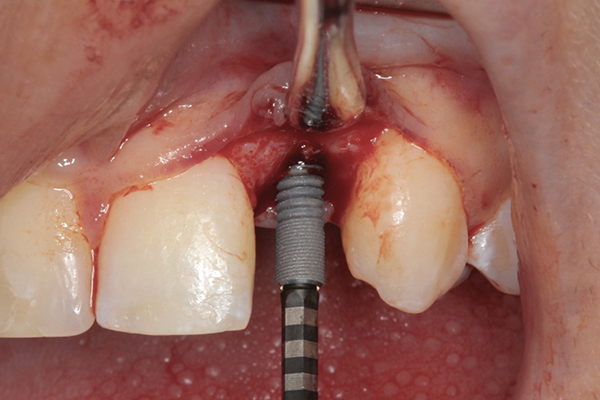

Fig 9 and Fig 10. An implant placed in site No. 10.

When the patient was 18 years old, an implant was placed in site No. 10 with no complications (Figure 9 and Figure 10). Three months later, a periapical radiograph was taken, the implant was torque tested, and a healing abutment (3 mm by 4 mm by 4 mm) was placed.

Two-and-a-one-half weeks later, the prosthodontist made an open-tray implant-level impression, which was sent to the laboratory for creation of a soft-tissue model, custom abutment, provisional, and zirconia coping. The 3-mm custom abutment was inserted with a resin jig and, on verification with a periapical radiograph, torqued to 15 Ncm, according to the manufacturer’s recommendation. The provisional was placed and modified following initial tissue blanching to raise and scallop the tissue, develop a proper emergence profile, and prosthetically guide the soft-tissue development.34 After the screw-access hole was filled with polytetrafluoroethylene tape, the provisional was cemented by carefully painting a thin layer of temporary cement to minimize excess and meticulously checked for complete cement removal.